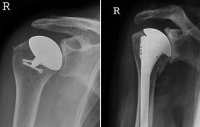

Abbildung 3: Inverse Prothese

Mineralstoffwechsel

Prothese

Röntgenbild

Schultergelenk